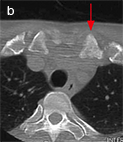

b:鎖骨CT

図❷ CT画像では、左側下顎骨体部と左側鎖骨胸骨端の骨髄にhigh density areaを認める。MRI画像で同部の骨髄は、STIRで高信号を呈する

画像所見:パノラマX線写真では、67部の下顎骨体部に淡いすりガラス様のX線不透過像が認められた(図❶)。CT画像では、左側下顎骨体部の骨髄に high density area を認め、また、左側鎖骨胸骨端にも同様の像が認められた。MRI画像で同部の骨髄は、T1W1で低信号、STIRで高信号を呈していた(図❷)。